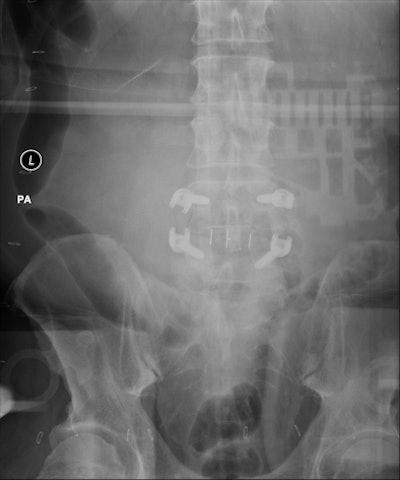

![]() |

| Backscatter artifact expressed itself as an outline of DR system electronics imposed on high-exposure images of large patients or long exposures. |

Mayo physicists fitted a phantom with pads of synthetic fat to reproduce the artifact under controlled conditions.

Based on this inquiry, they discovered that a lack of lead shielding -- possibly removed from the detector to reduce its weight and make it more marketable -- produced conditions that allowed the backscatter artifact to appear.

The problem disappeared when a lead apron was draped over the detector. The vendor then responded by taping a thin sheet of lead to the back of the detector.